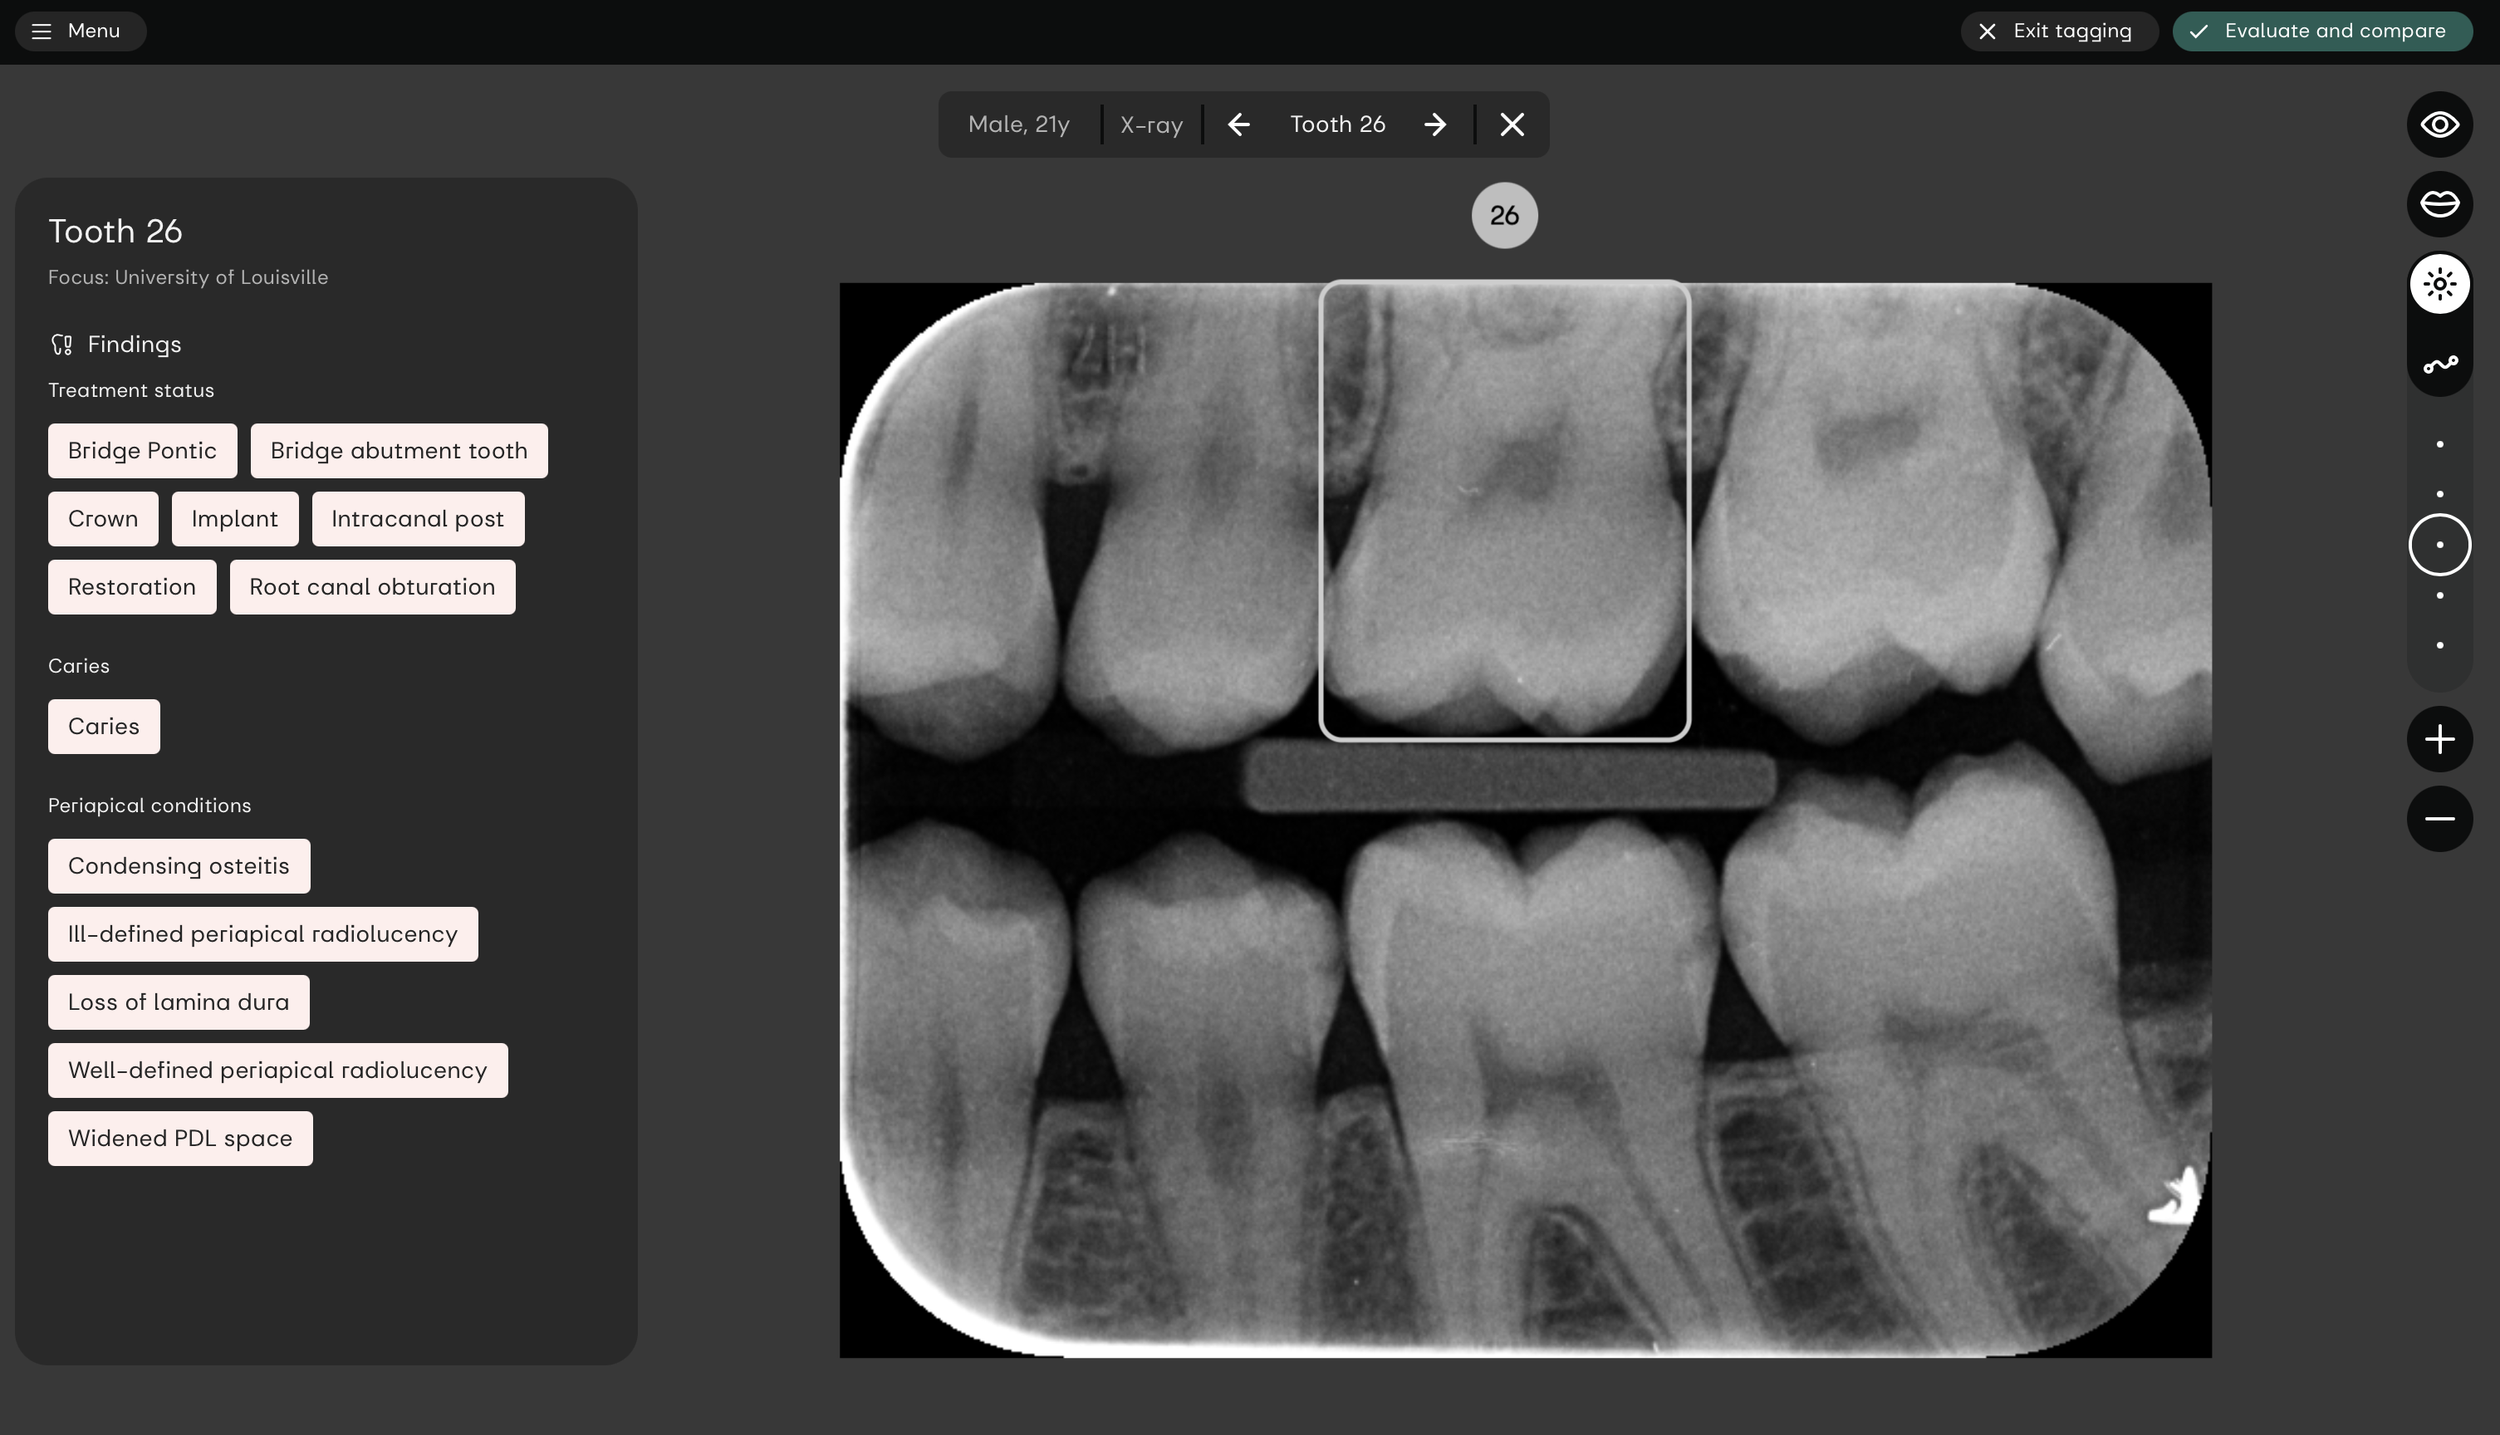

Clinical AI:D

app for dentists

MDR-ready dental X-ray diagnostics for clinics. A second pair of eyes that helps improve diagnostic consistency and reduce missed treatment opportunities.

for dental students and universities.

Learn to interpret dental X-rays

and practice accurate diagnose

with interactive, real-world cases.

Anytime, anywhere.